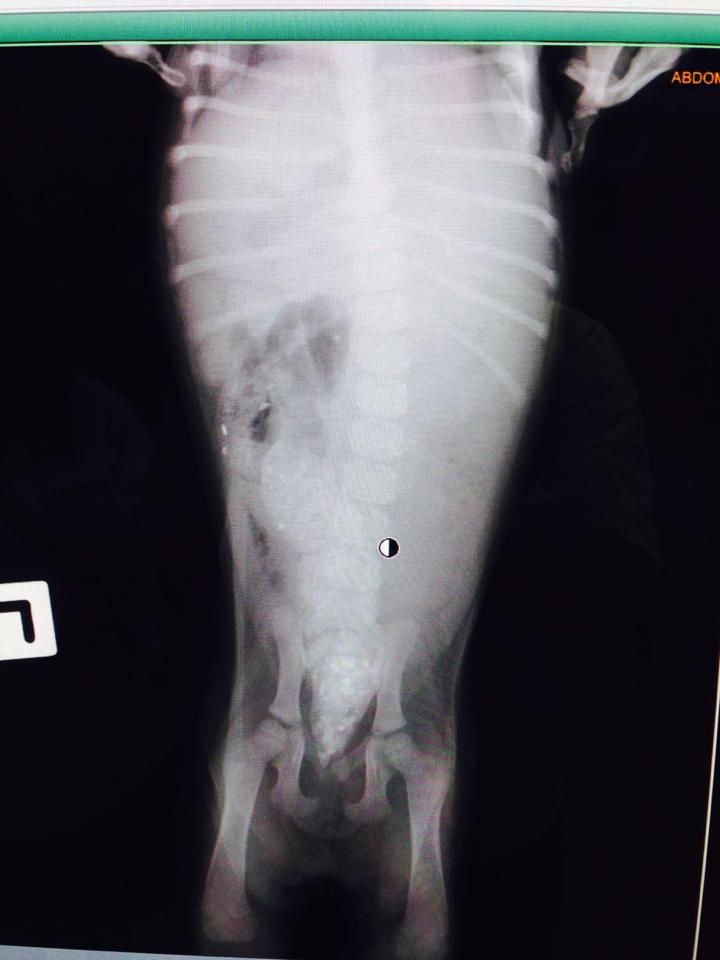

ภาพเอ็กซเรย์น้องค่ะ

ซึ่งวันนี้เราได้นำน้องเข้าไปรักษาที่โรงพยาบาลสัตว์มหาวิทยาลัยมหานคร ซึ่งพอดีเราเรียนอยู่ที่นี่ค่ะ อยากจะรักษาน้องให้หายดีก่อนแล้วจะดำเนินการหาบ้านให้น้องต่อไปค่ะ ก็เบื้องต้นได้ทำการตรวจเลือดและเอ็กซเรย์ ซึ่งภาพที่ออกมาคือเห็นอุจจาระค้างอยู่ในลำไส้ก่อนถึงอุ้งเชิงกราน คุณหมอบอกว่าถ้าอยากรู้ว่าปลายของลำไส้จะยาวถึงประมาณไหนจะต้องให้น้องกลืนสีเพื่อเอ็กซเรย์ดูอีกที จะได้วางแผนการรักษาถูกค่ะ คุณหมอแจ้งมาว่าจะทำการรักษาโดยการผ่าตัดให้ปลายของลำไส้ออกมาทางด้านรูทวาร น้องจะมีคุณภาพชีวิตที่ดีขึ้น อึและฉี่จะได้ออกถูกทางไม่ปนกันซึ่งหากปล่อยทิ้งไว้จะเกิดปัญหาตามมาในอนาคต พรุ่งนี้จะให้น้องกลืนสีในช่วงเช้าและถ่ายเอ็กซเรย์อีกครั้ง จะผ่าตัดได้เร็วที่สุดราวๆวันพุธนี้ค่ะ ให้กำลังใจน้องด้วยนะคะ